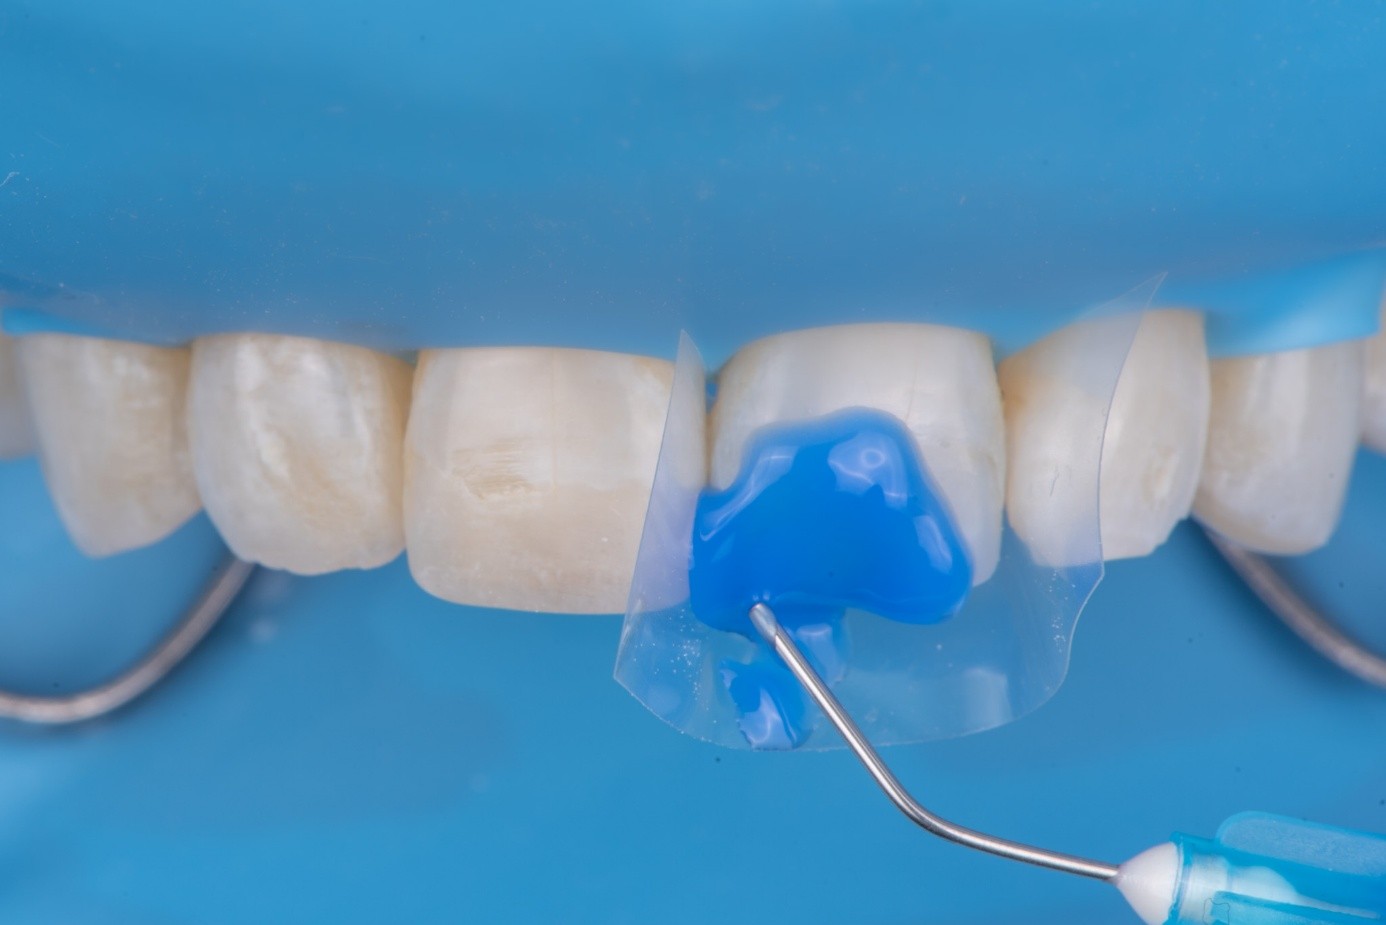

After achieving rubber dam isolation, the fractured composite segment was first air-abraded with aluminum oxide particles to clean and roughen the surface. It was then etched with phosphoric acid for 60 seconds, rinsed, dried, and treated with silane to enhance chemical adhesion (Figure 18 through Figure 20).8,9

The tooth surface was similarly air-abraded to remove biofilm and aged resin remnants, then selectively etched with phosphoric acid. Silane was applied intraorally to the exposed composite surface to promote bonding between the old and new composite layers.10 Following this, a universal bonding agent was applied to both the tooth surface and the fractured composite segment (Figure 21 through Figure 24).

(21.) Intraoral view after rubber dam isolation, showing prepared surfaces: both sandblasted and etched, with silanization applied only to the composite surface, ready for reattachment.

Figure 21

(22.) Intraoral view after rubber dam isolation, showing prepared surfaces: both sandblasted and etched, with silanization applied only to the composite surface, ready for reattachment.

Figure 22

(23.) Intraoral view after rubber dam isolation, showing prepared surfaces: both sandblasted and etched, with silanization applied only to the composite surface, ready for reattachment.

Figure 23

(24.) Intraoral view after rubber dam isolation, showing prepared surfaces: both sandblasted and etched, with silanization applied only to the composite surface, ready for reattachment.

Figure 24